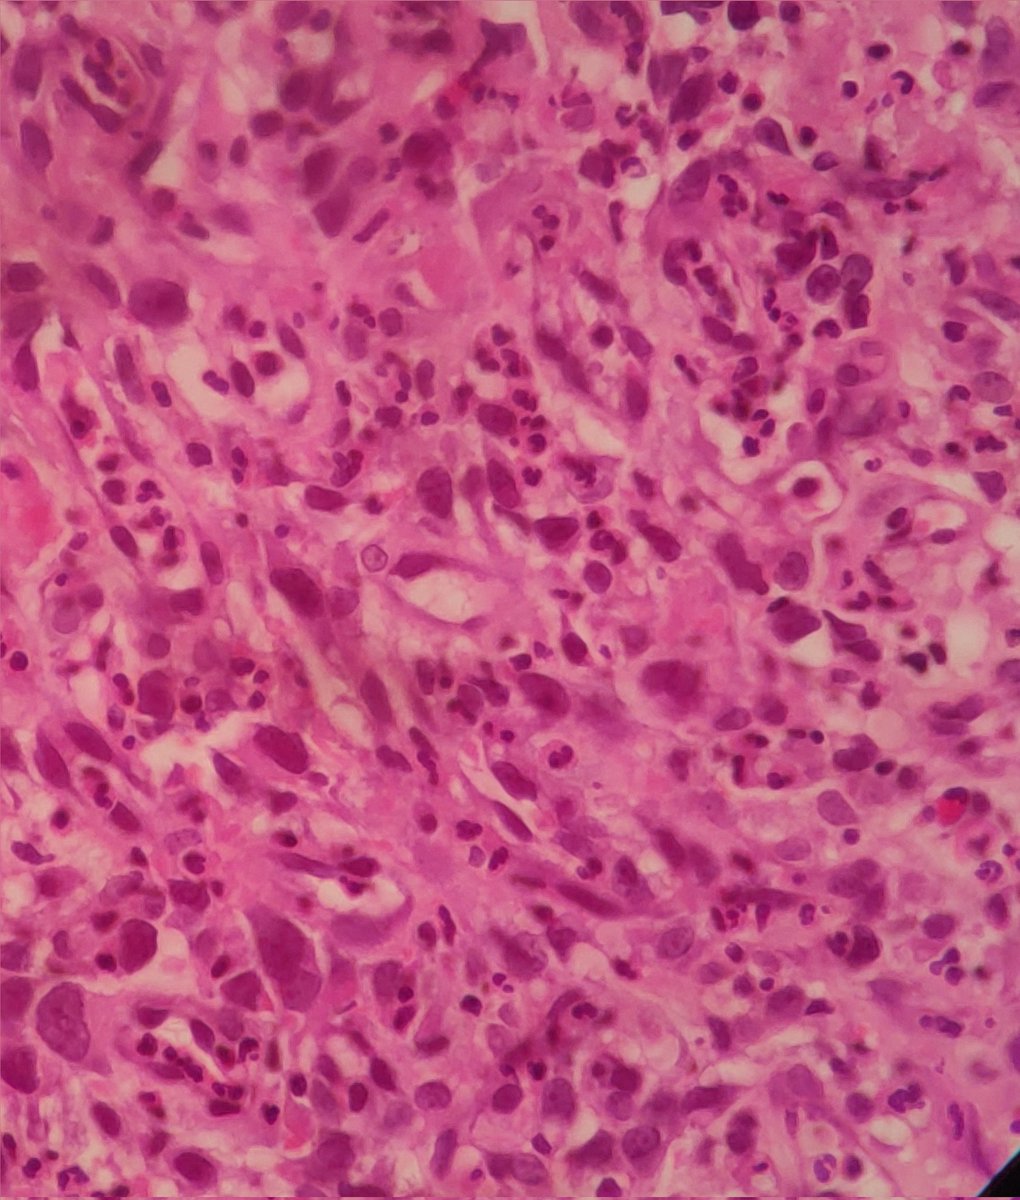

Spotted this wretched tumour in the endometrium of a poor 60 year old lady #pathology #twitterpath #gynaecpathology

docnax's tweet image. Spotted this wretched tumour in the endometrium of a poor 60 year old lady #pathology #twitterpath #gynaecpathology